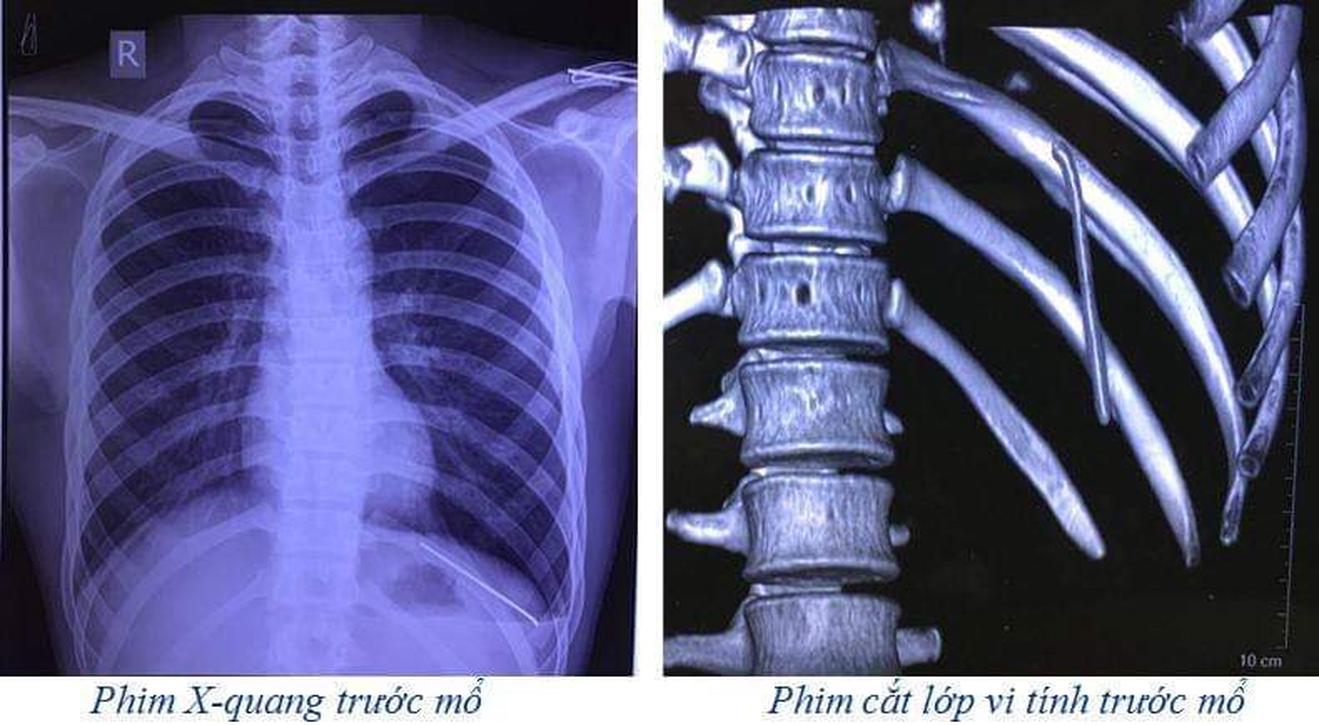

Sau khi thăm khám, các bác sĩ đã chỉ định chụp X-quang và cắt lớp vi tính lồng ngực. Kết quả phim cắt lớp vi tính lồng ngực cho thấy: Dị vật dạng kim khí trong khí màng phổi trái, tràn khí khí màng phổi trái.

Các bác sĩ chỉ định: Phẫu thuật nội soi ngực trái để lấy dị vật và xử lý tràn khí khoang màng phổi trái. Sau phẫu thuật 1 ngày, người bệnh ổn định, đã được rút bỏ dẫn lưu khoang màng phổi, đi lại và ăn uống gần như bình thường.

Bác sĩ Dương Xuân Phương, người trực tiếp phẫu thuật cho bệnh nhân chia sẻ: Đây là một ca bệnh hy hữu, hiếm gặp, ngay cả các bác sỹ trong hội đồng duyệt mổ đã làm việc rất lâu năm rồi cũng ngạc nhiên với ca bệnh này. Nguyên nhân là do chiếc đinh đó di chuyển từ vị trí xương đòn trái theo thời gian nó rơi tự do vào trong khoang màng phổi trái.

Trước khi mổ ca bệnh này thì kíp phẫu thuật và kíp gây mê hồi sức đã chuẩn bị tối đa các phương án đề phòng nếu có tổn thương hệ thống mạch máu lớn và tim. Rất may mắn là chiếc đinh chỉ làm rách nhu mô phổi gây tràn khí khoang màng phổi trái.